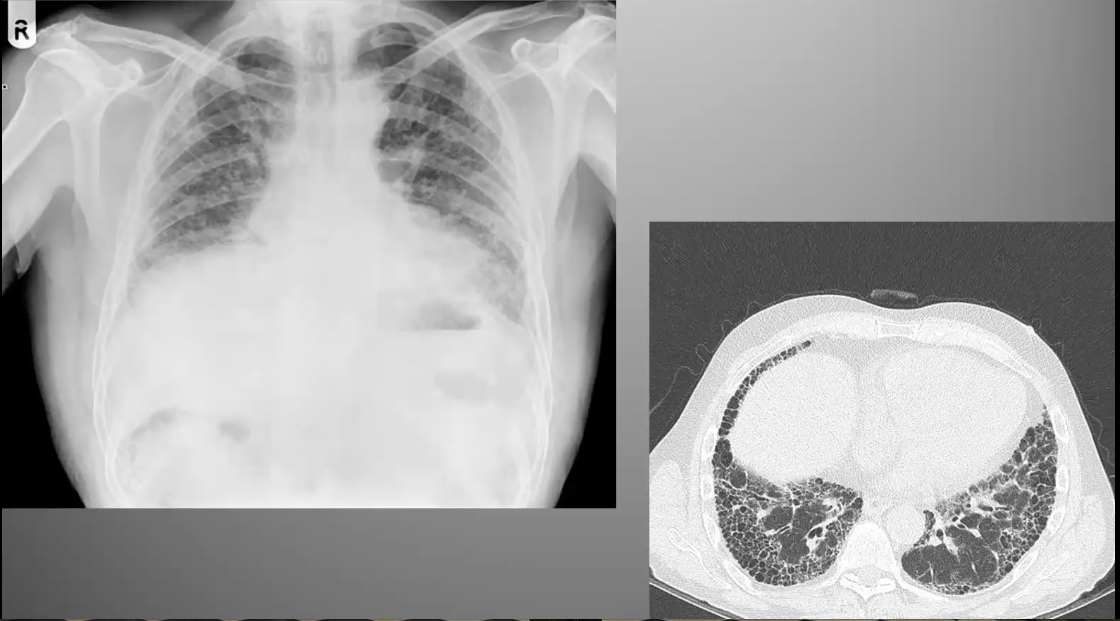

What’s your diagnosis?

Ground Glass: Hypersensitivity Pneumonitis